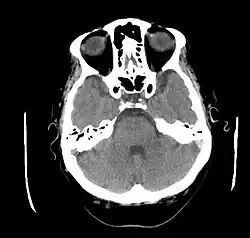

CT głowy pacjenta z objawami neurologicznymi w przebiegu choroby Behçeta, hiperdensyjna lewa zatoka esowata | |